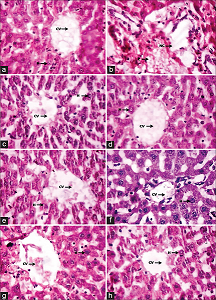

3.4. Effect of Probioticated Juices on Histopathalogical Changes in Rats

Oral administration of probioticated tomato, carrot, and tomato plus carrot fruit juices containing L. sphaericus significantly modulated the changes of histopathological architecture. Figure 3 shows the architecture of normal and treated liver tissue of rats, whereas Figure 4 shows that architecture of normal and treated adipose tissue of rats. In these, Figures 3a and 4a refer to normal diet-fed rat liver and adipose. Figures 3b and 4b refer to HFD-fed rat liver and adipose, and some architectural variations were found in HFD-fed rats. The recovery of architecture found in probioticated juice-treated rats (Figures 3c and 4c refer to HFD+C1; Figures 3d and 4d refer to HFD+C2; Figures 3e and 4e refer to HFD+T1; Figures 3f and 4f refer to HFD+T2; and Figures 3g and 4g refer to HFD+MX), whereas lovastatin (HFD+STD)-treated rats, tissue architecture was similar to normal diet-fed rats in architecture [Figures 3h and 4h].

![]() | Figure 3: Liver histopathological changes of normal and probioticated juice supplemented rats (a) normal; (b) HFD; (c) HFD+C1; (d) HFD+C2; (e) HFD+T1; (f) HFD+T2; (g) HFD+MX; (h) HFD+STD [Click here to view] |

![]() | Figure 4: Adipose histopathological changes of normal and probioticated juice supplemented rats (a) normal; (b) HFD; (c) HFD+C1; (d) HFD+C2; (e) HFD+T1; (f) HFD+T2; (g) HFD+MX; (h) HFD+STD [Click here to view] |

The swelling of hepatocytes together with excessive cytoplasmic vacuolation and vascular congestion was observed in the liver histopathological changes in HFD group rats (Group 2). The recovery of hepatocytes was observed in probioticated juice-supplemented rats, and these results were in agreement with El-Moneim and ElMouaty [56]. There was also an increase in the amount of white adipose tissue surrounding the kidney, and an increased size of adipocytes was observed in HFD rats compared with the rats received PCJ, PTJ, and PCT together with HFD. These results were in agreement with Nanna et al. [57] and they reported that histological changes were observed in aqueous leaf extract of Tiliacora triandra administrated to HFD mice.